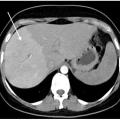

Syndrome de Budd-Chiari

Le syndrome de Budd-Chiari (SBC) est une affection rare caractérisée par une obstruction du drainage veineux hépatique, commençant au niveau des veinules hépatiques jusqu’à la partie terminale de la veine cave inférieure. Il peut se manifester par un tableau d’hépatite fulminante, notamment en cas d’obstruction complète des trois…